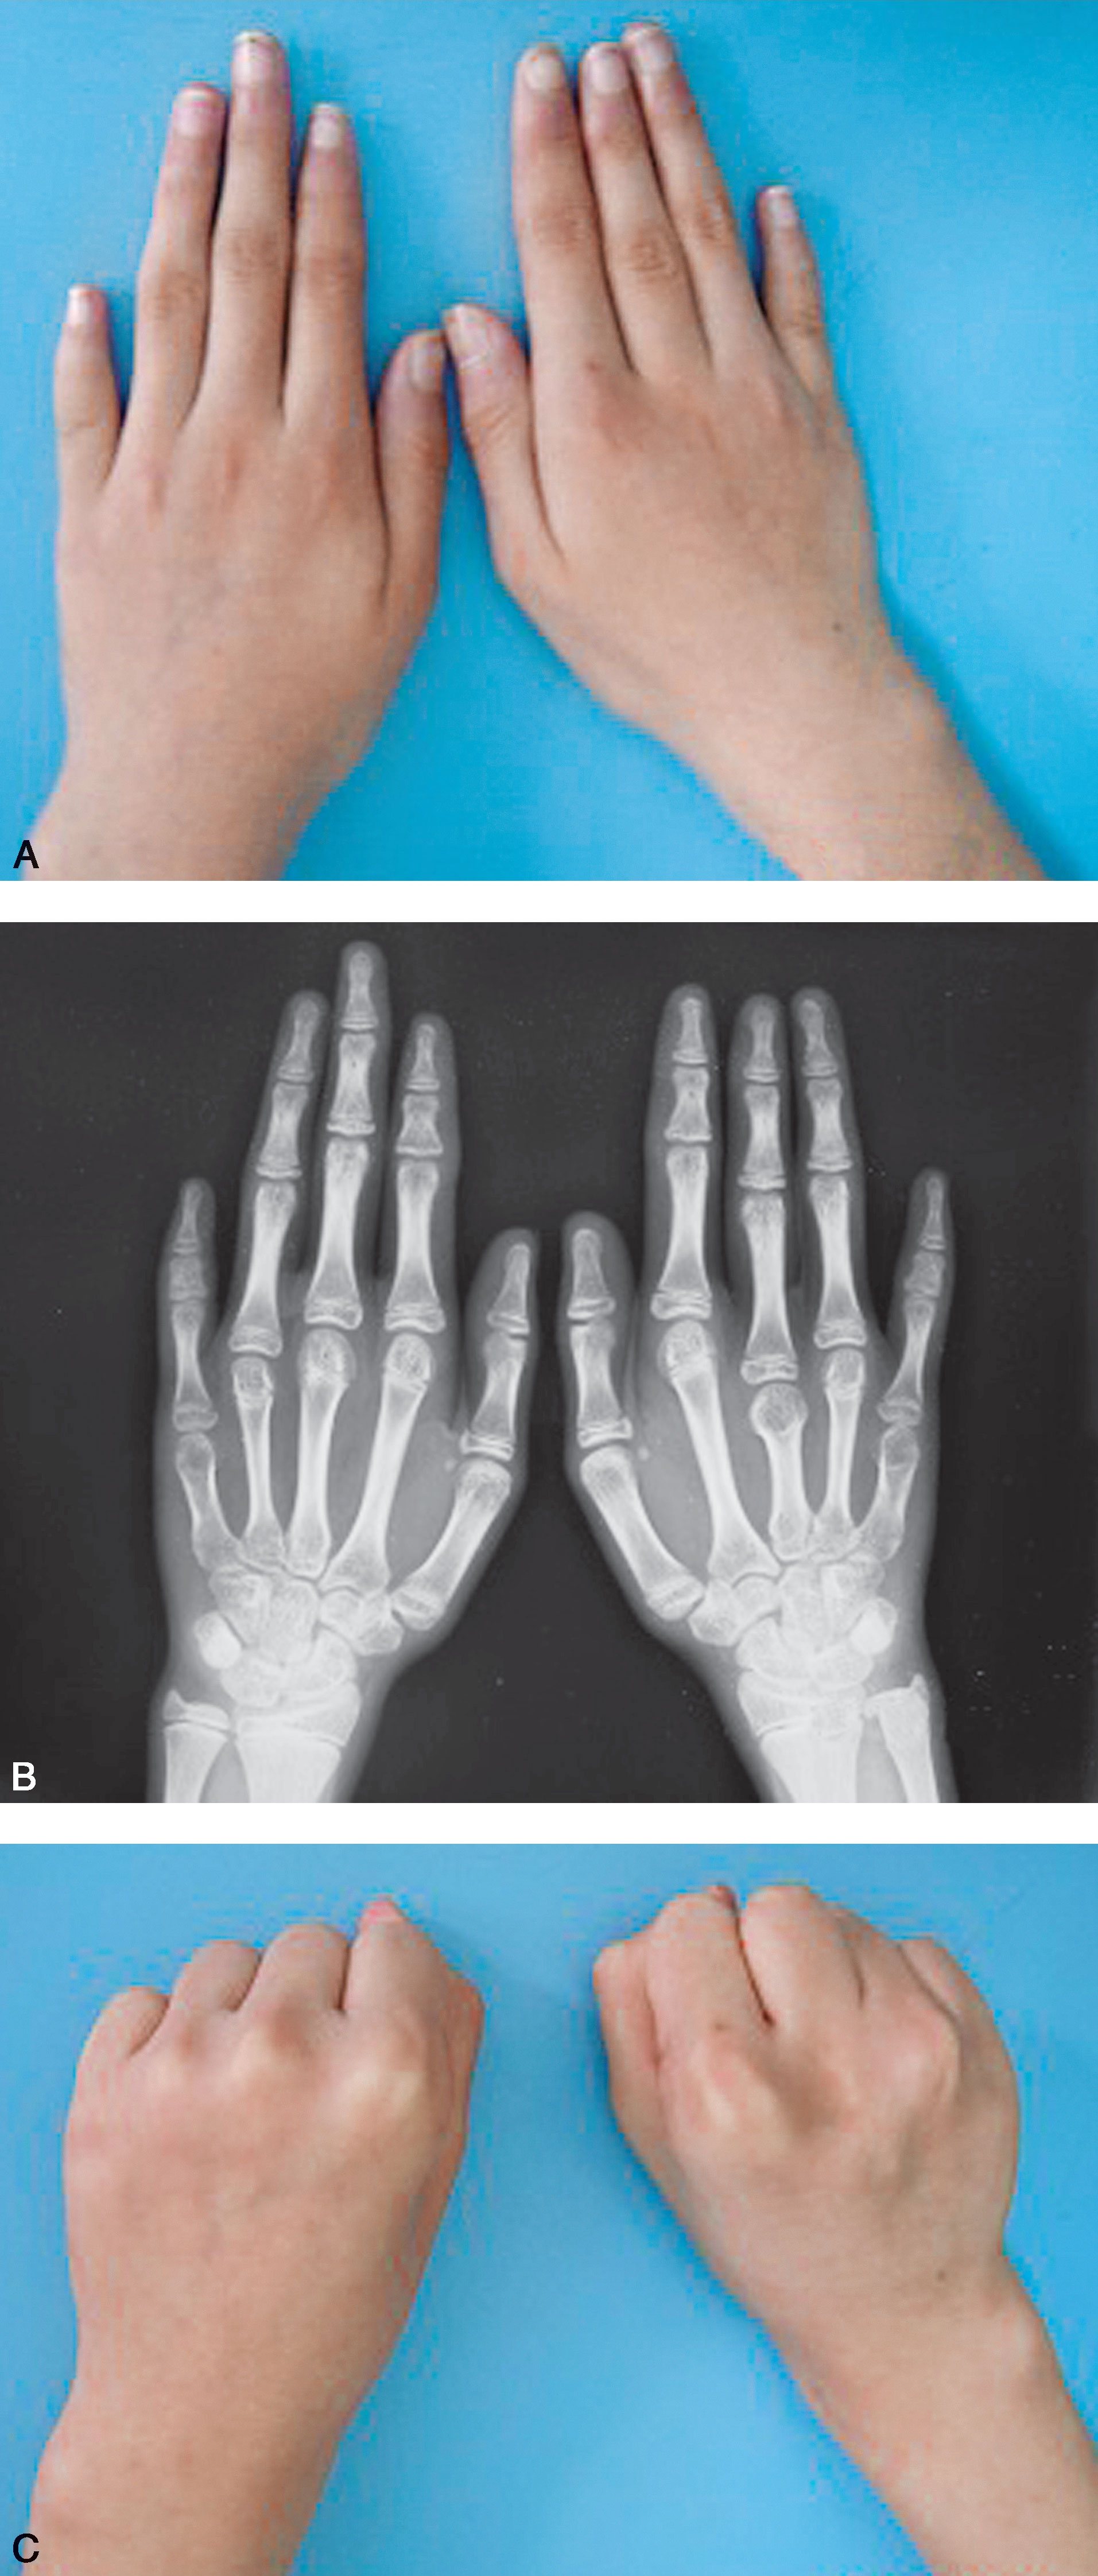

图1-2-45 掌骨生长不足病例

A.双手手指短小(右侧中、小指,左侧示、小指);B.X 线片显示右侧第Ⅲ、Ⅴ掌骨短小,左侧第Ⅴ掌骨短小,左示指中节指骨、双小指中节指骨短小;C.患手握拳时可见掌骨短小的手指掌指关节塌陷,关节屈曲受限